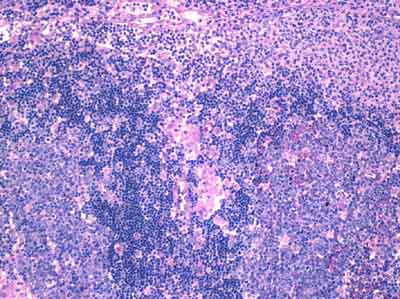

Toxoplasmosis in Lymph Nodes

At the lower left and right are hyperplastic follicles with aggregates of epithelioid histiocytes encroaching on them from the middle. On the upper right are hyperplastic monocytoid B-cells. The follicles, histiocytes, and monocytoid B-cells compose the classic triad. |